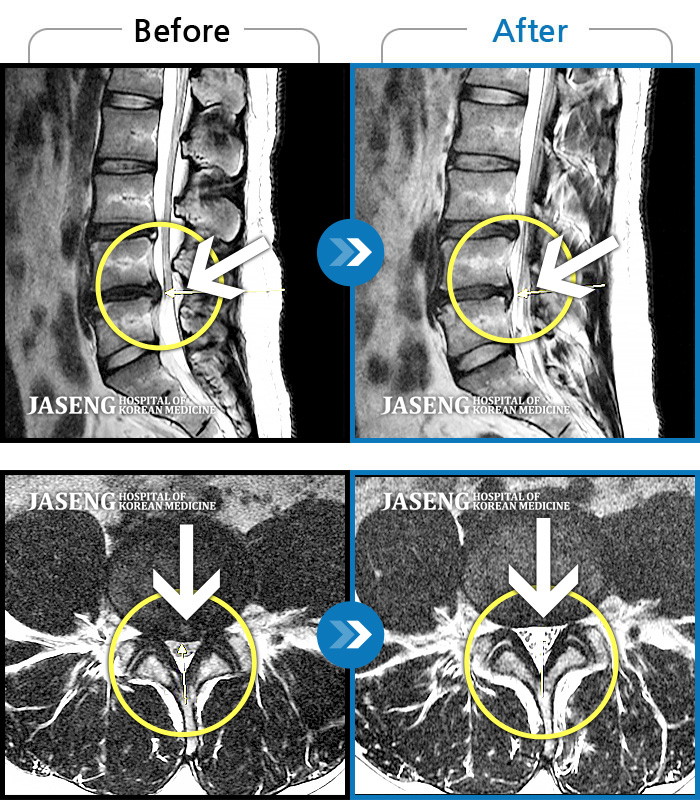

MRI 치료사례

좌측 하요추부 통증과 좌측 하지 전면 비증